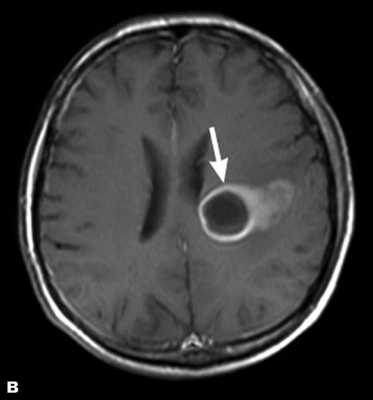

Абсцессы на МРТ выглядят как крупные или мелкие кисты, но заполнены гнойным содержимым и окружённые зоной выраженного отека вещества мозга.

Злокачественная опухоль на МРТ

Злокачественные опухоли характеризуются инвазивностью, то есть врастанием в здоровые ткани, поэтому контуры таких образований нечеткие и неровные, а потому достоверно определять границы таких опухолей довольно сложно. Кроме того, структура злокачественной опухоли часто бывает неоднородна за счет распада (некроза), кровоизлияния и коллоидной дегенерации. Вокруг злокачественной опухоли, как правило, выявляется выраженный перифокальный отек, который может приводить к смещению срединных структур головного мозга и появлению аксиальной дислокации. Также могут быть выявлены признаки метастазирования.

После введения контрастного вещества метастатические очаги четко отграничиваются. Периферическая часть отграничивается от паренхимы четким кольцом за счет отека, некроза, центральной кистой.